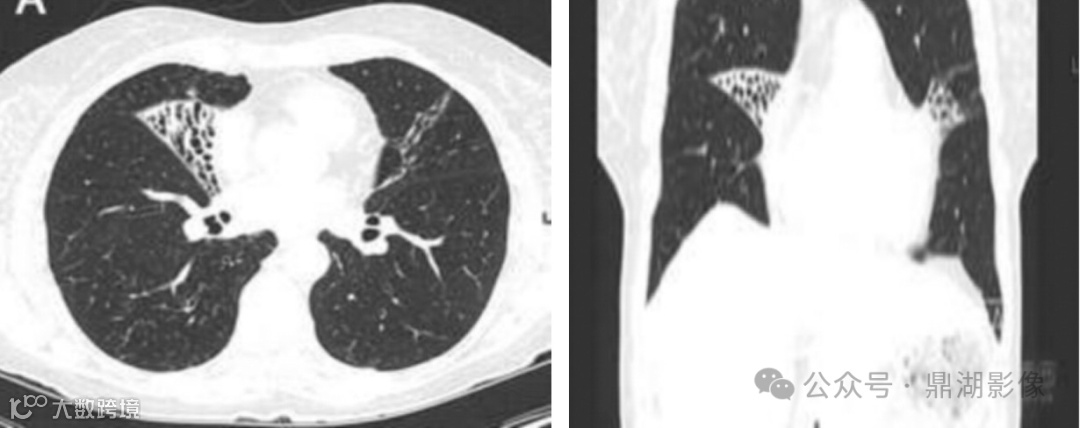

双肺多发支气管扩张伴感染,以右肺中叶、左肺上叶下舌段为著;余双肺散在多发小结节、小结片及小斑片影,部分代谢轻度增高,考虑感染性病变;

病灶累及左肺舌叶与右肺中叶,是温夫人综合征的典型表现。(Yu JA, et al. Eur J Cardiothorac Surg 2011)

支气管扩张及结节为主型病变:以支气管扩张伴周围小叶中心结节为主,可合并空洞、斑片影等其他征象,表现为树芽征的细支气管炎、支气管管壁增厚的节段性支气管扩张及伴有黏液堵塞是疾病活动的表现。右肺中叶、左肺舌段是 NTM 患者支气管扩张累及的常见部位

NTM与肺结核的CT征象有一定相似性,但仍有其特征表现。NTM双肺病变比肺结核要常见,前者更容易出现薄壁空洞 (直径>3 cm) 和支气管扩张,且支气管扩张好发于右肺中叶和左肺上叶舌段